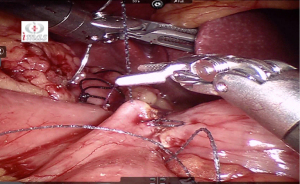

Jejuno-jejunal anastomosis

Window created in Jejunum mesentery just proximal to Gastro-jejunostomy (towards left side) and jejunum transacted using white/tan-60 mm cartridge thus creating a biliopancreatic limb of 100 cm (Figure 13).

Roux limb measured for 100 cm from Gastro-jejunostomy till we reach the previously placed marking sutures. Enterotomies made at 100 cm mark and in the biliopancreatic limb.

Jejuno-jejunostomy (side to side) is made using blue/tan 60 mm cartridge) (Figures 14,15).

Enterotomy closed in single layer using non-absorbable sutures from below upwards in a continuous fashion (Figure 16).